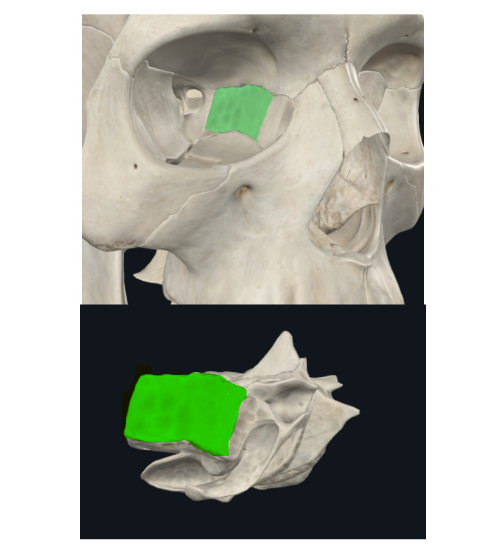

Lámina cribosa del etmoides

Lados se articulan con el frontal

Forma parte del piso de la fosa craneal anterior

Perforada por múltiples orificios, por eso el nombre de cribiforme

Dos apófisis alares que articulan con el frontal, creando el foramen cecum

Foramen Caecum

Llamado también Agujero Ciego

Agujeros etmoidales

Anterior y posterior